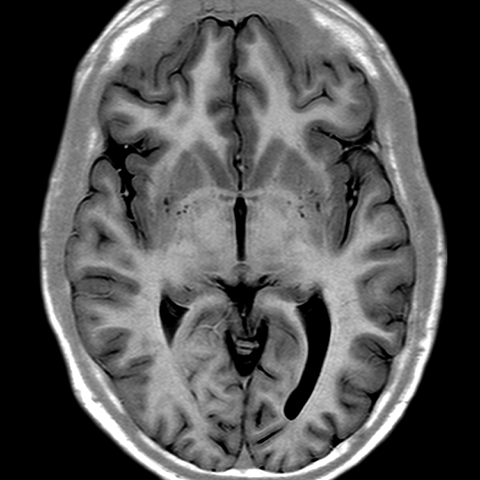

Cerebral Hemispheres, MR (normal) [3 of 9]